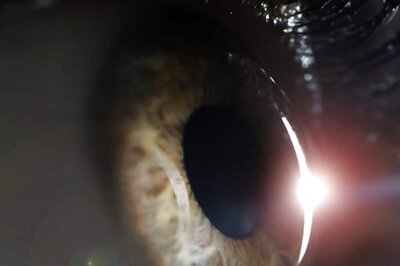

Tips to Take Care of Your Eyes Post-cataract Surgery

The Head Medical Officer for Cataract & Trauma at Sankara Eye Hospital in Shimoga, Dr. Mahesha S., provides advice on how to care for eyes following cataract surgery